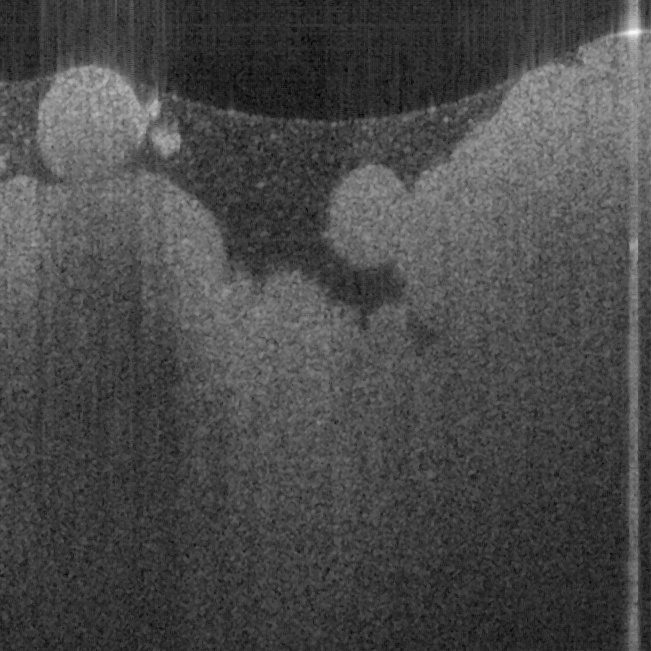

Fig. 17 shows ex vivo images of coronary artery of rabbit with forward-view (a, b) probe with

ball lens #16 and side-view (c, d) probe with GRIN lens #5 acquired by our catheter-based

complex SS-OCT using our 3x3 Mach-Zehnder interferometer with unbalanced differential

detection technique with image size of 2.5x2mm by scanning the probe along the artery (a, c)

and scanning cross the artery (b, d). Three layers of tunica intima, tunica media, and tunica

adventitia for the coronary artery are viewed clearly as indicated by the gray, black, and

white arrows in all four images in Fig. 17. The fine layers of muscle and elastic fiber in the

tunica media of the coronary artery are shown obviously in the images obtained by

scanning the probe cross the artery.

Fig. 17. Ex vivo images of coronary artery of rabbit scanning along the artery (a, c) and

scanning cross the artery (b, d) with forward-view probe (a, b) with ball lens #16 and side-

view (c, d) probe with GRIN lens #5 acquired by our catheter-based complex SS-OCT using

our 3x3 Mach-Zehnder interferometer with unbalanced differential detection technique.